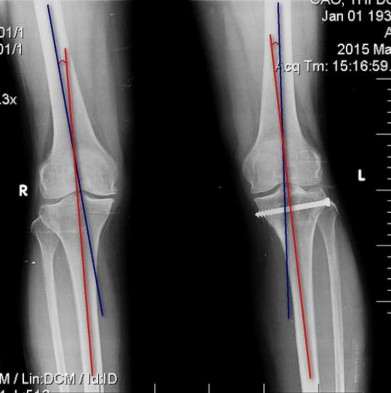

Hình 2.14. Cách xác định góc chày đùi.

2.6.2.3. Góc chày đùi và độ khác biệt góc chày đùi

Góc chày đùi được xác định theo các bước: (Hình 2.14)

- Vẽ đường thẳng trục xương đùi

- Vẽ đường thẳng trục xương chày

- Góc tạo bởi 2 đường thẳng này là góc chày đùi.

- Độ khác biệt góc chày đùi là hiệu số của góc chày đùi chân gãy và góc chày đùi chân không gãy.